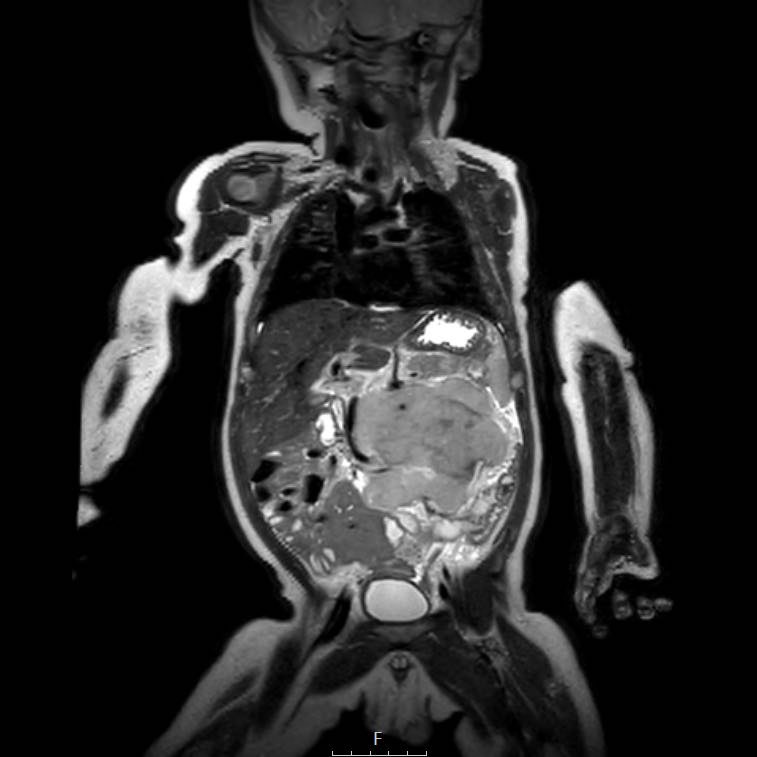

Hình ảnh MRI của một bé gái chín tháng tuổi có khối u ở bụng trái. MRI cho thấy khối u tuyến thượng thận trái, một phần đặc, một phần nang. Có nhiều di căn gan.

Khối u đã được sinh thiết. Có tình trạng chảy máu liên tục qua kim dẫn đường. Vào cuối thủ thuật, hai nút bọt gelatin đã được đặt vào (các dải tăng âm (mũi tên)).